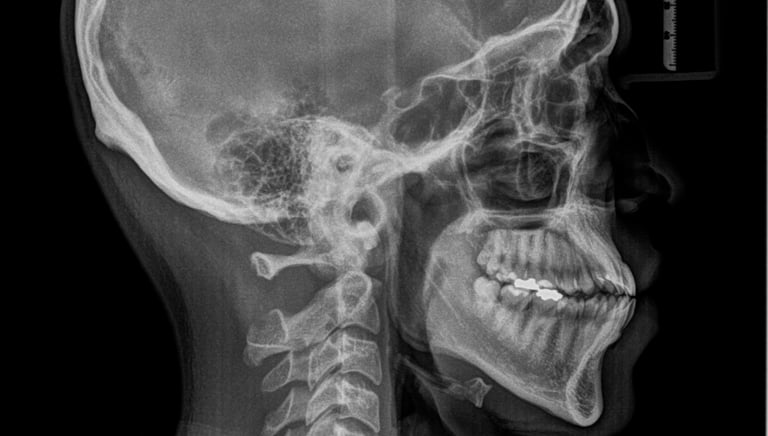

CEFÁLICA LATERAL

Permite la evaluación de la vía aérea, integridad de la bóveda palatina, ver senos paranasales y paladar duro, cefalometría y la impresión lateral de la columna cervical.